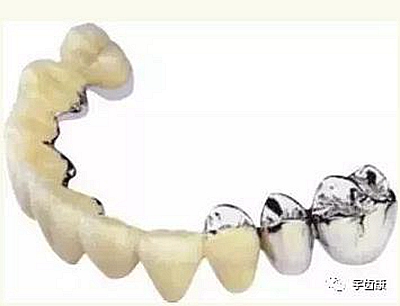

烤瓷牙結(jié)構(gòu)知識(shí)

烤瓷牙的設(shè)計(jì)方式